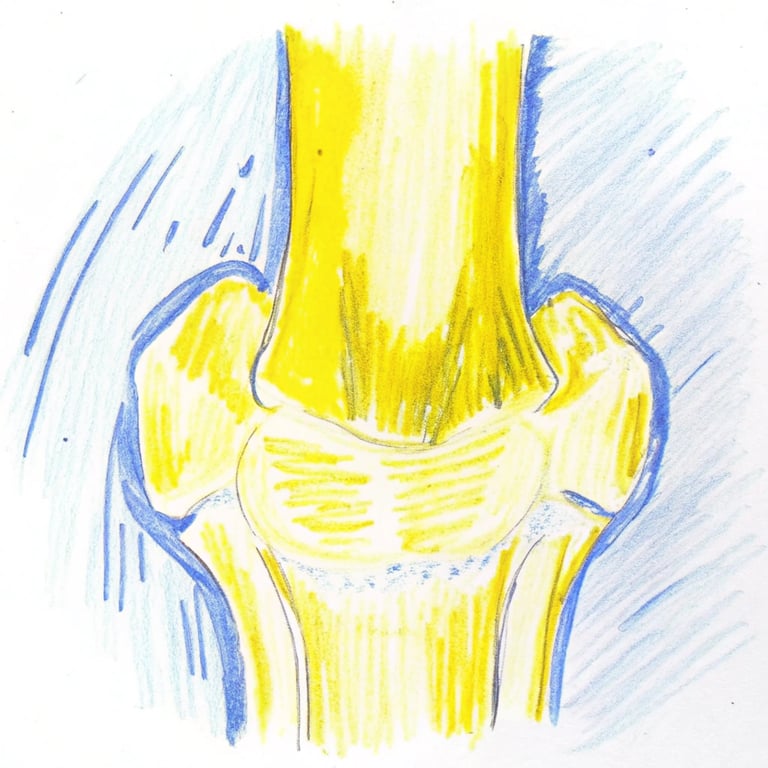

我們的膝關節是人體最大的承重關節,由大腿骨(股骨)、小腿骨(脛骨)和膝蓋骨(髕骨)組成。這些骨頭的接觸面都覆蓋著一層平滑且富有彈性的關節軟骨。這層軟骨就像一個避震墊,不僅能減少骨頭之間的摩擦,讓關節活動順暢,還能吸收走路、跳躍時產生的衝擊力。然而,隨著年齡增長,關節軟骨會逐漸的失去水分和彈性,慢慢磨損以及變薄、變粗糙。

當軟骨磨損嚴重時,骨頭與骨頭之間缺乏軟骨保護,直接摩擦,就會引起關節發炎、疼痛。為了穩定關節,骨骼邊緣還可能增生出骨刺,導致關節空間變窄,活動更加受限。